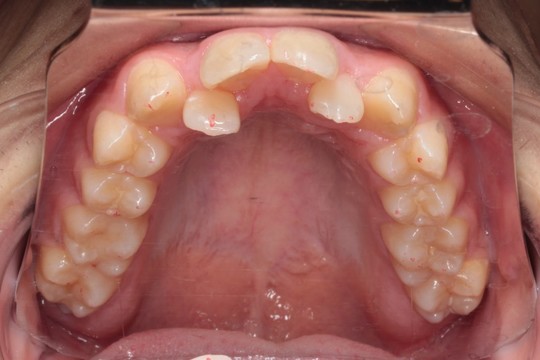

上顎 治療前

上顎 治療後

調布市の20代男性

主訴:前歯のデコボコを直したい

使用装置:インビザライン

治療期間:約2年

治療費用:93.5万円(税込)

治療結果:叢生が改善されました

今回の症例は写真のように上の中心から2番目の歯が左右とも奥に入り込んでいてかなりスペースのない状態でした